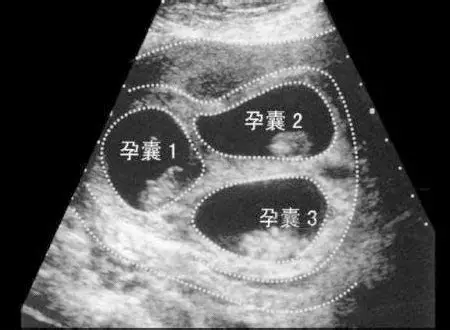

2、B超检查:通过B超检查,能够明确的看见子宫中拥有的胎囊数量,在妊娠晚期,还可看见颅骨、脊柱的声像图,通过B超诊断多胎准确率100%;